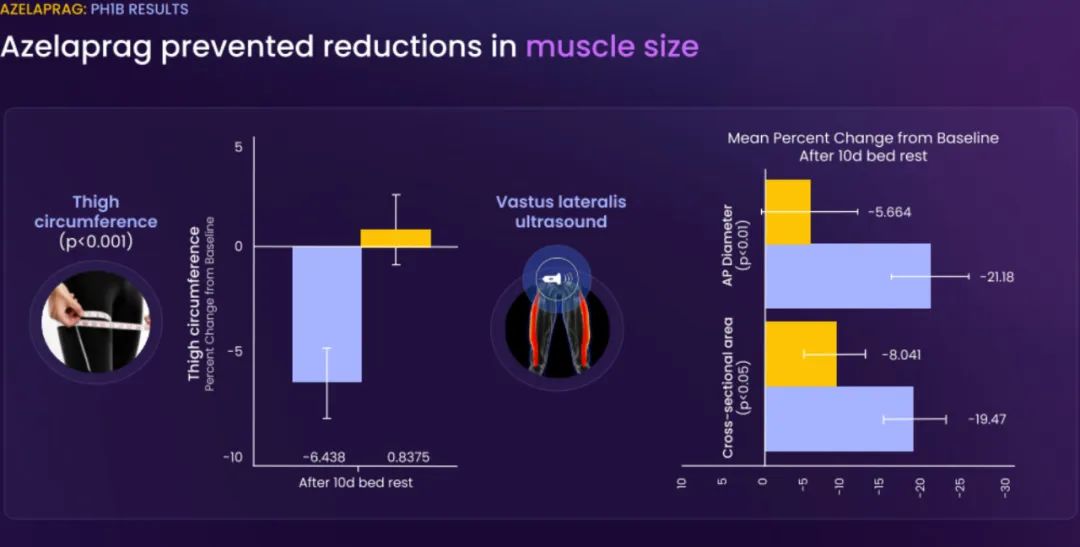

这些临床前结果得到BioAge Labs在卧床老年人中进行的 1b 期临床试验的支持,在该试验中,BioAge Labs观察到在 10 天内接受 azelaprag 治疗的受试者的肌肉萎缩减少、肌肉质量保持良好并且新陈代谢得到改善。